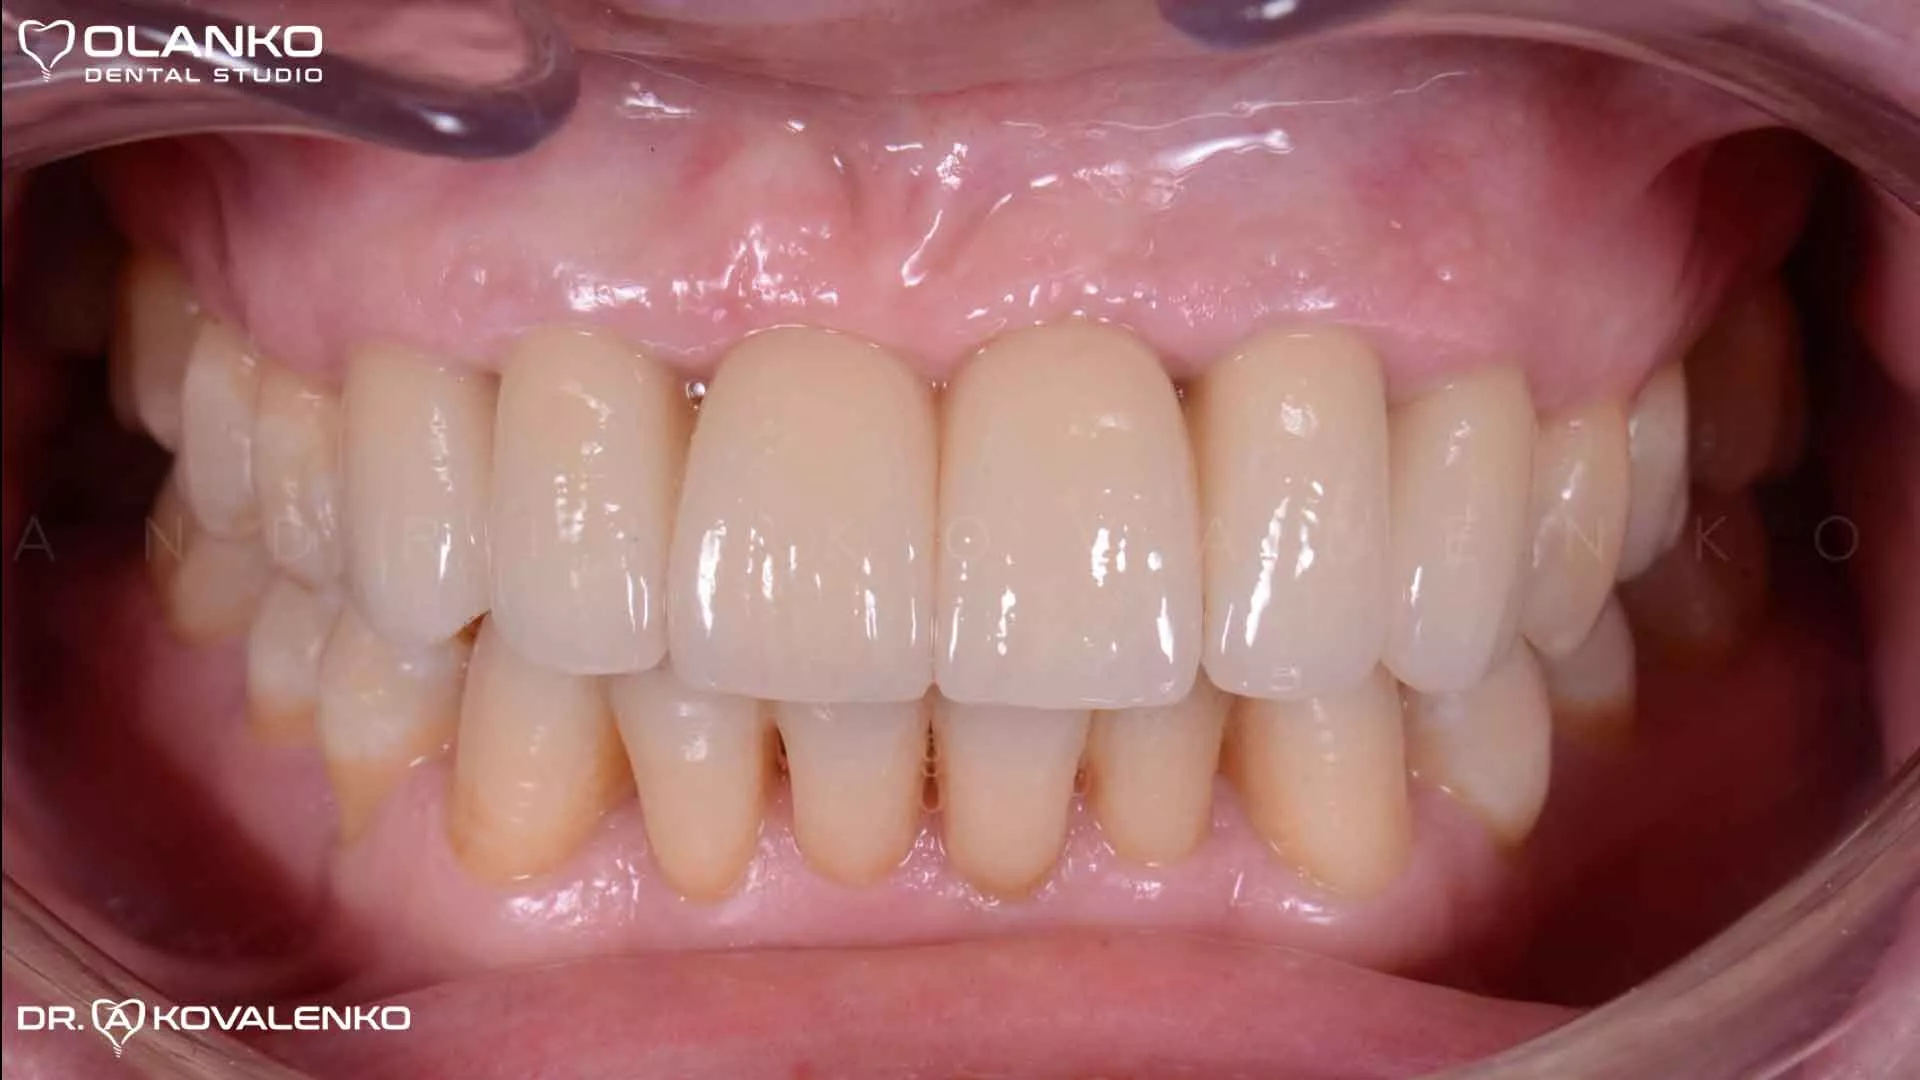

Фото в роті після закінчення протезування на імплантатах